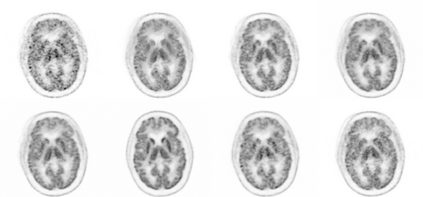

Due to various physical degradation factors and limited counts received, PET image quality needs further improvements. The denoising diffusion probabilistic models (DDPM) are distribution learning-based models, which try to transform a normal distribution into a specific data distribution based on iterative refinements. In this work, we proposed and evaluated different DDPM-based methods for PET image denoising. Under the DDPM framework, one way to perform PET image denoising is to provide the PET image and/or the prior image as the network input. Another way is to supply the prior image as the input with the PET image included in the refinement steps, which can fit for scenarios of different noise levels. 120 18F-FDG datasets and 140 18F-MK-6240 datasets were utilized to evaluate the proposed DDPM-based methods. Quantification show that the DDPM-based frameworks with PET information included can generate better results than the nonlocal mean and Unet-based denoising methods. Adding additional MR prior in the model can help achieve better performance and further reduce the uncertainty during image denoising. Solely relying on MR prior while ignoring the PET information can result in large bias. Regional and surface quantification shows that employing MR prior as the network input while embedding PET image as a data-consistency constraint during inference can achieve the best performance. In summary, DDPM-based PET image denoising is a flexible framework, which can efficiently utilize prior information and achieve better performance than the nonlocal mean and Unet-based denoising methods.